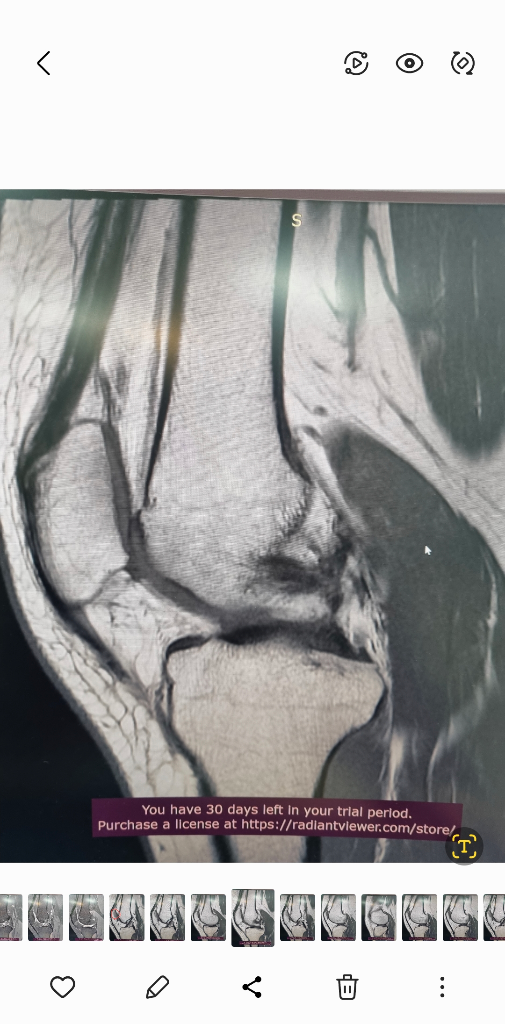

1. 추벽이 아닙니다.

2. 슬개골 관절면에 외상으로 인한 골수부종입니다.

3. 관절면 손상여부는 첨부해주신 영상만으로 알 수 없습니다